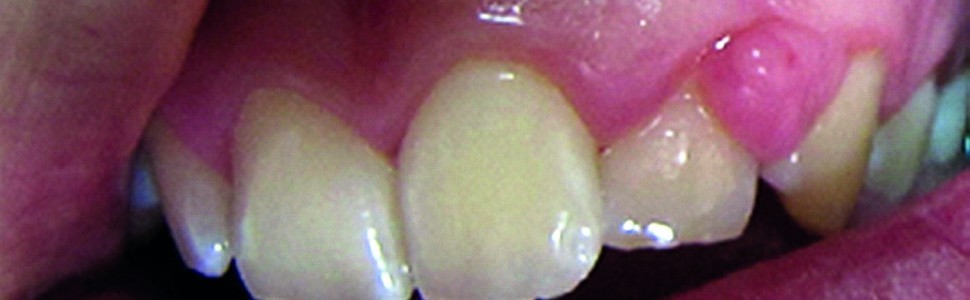

Kobiety w ciąży potrzebują szczególnej opieki stomatologicznej. W tym okresie mogą wystąpić różne zmiany na błonie śluzowej jamy ustnej, m.in. zapalenia dziąseł czy perimolysis. Z tego powodu Alliance for a Cavity-Free Future (ACFF) opracowało zalecenia dotyczące profilaktyki, higieny oraz nawyków dietetycznych.

Pregnant women require special dental care. During pregnancy women are more susceptible to different condition such as changes on the mucous membrane, gingivitis or perimolysis. For this reason Alliance for a Cavity-Free Future (ACFF) elaborated detailed recommendations considering prevention, hygiene and dietary habits.